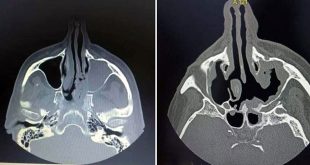

طرطوس-سانا بلغ عدد المصابين بالفطر الأسود في الهيئة العامة لمشفى الباسل بطرطوس خلال الشهرين الماضيين أربعة اشخاص توفي منهم اثنان في حين لا يزال مصابان يتلقيان العلاج في قسم العزل وهما بحالة جيدة حالياً. وبين مديرعام الهيئة الدكتور إسكندر عمار …